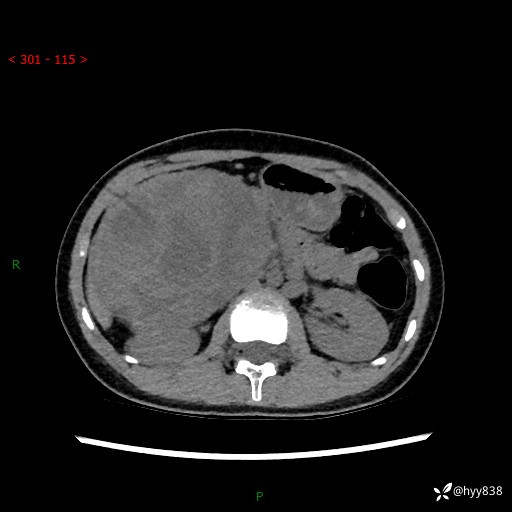

性别:女

年龄:13岁

简要病史:超声提示上腹部巨大包块

上腹部CT平扫

胰腺实性假乳头状瘤 (17)